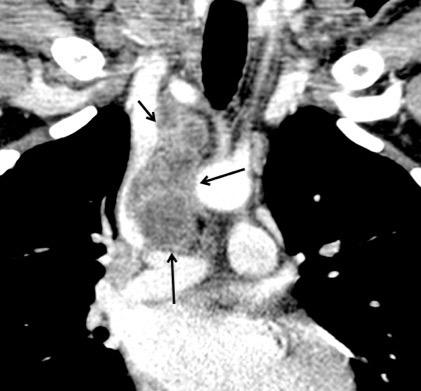

97. GANGLIOS CON CENTRO HIPODENSO

99.GANGLIOS CON HIPERCAPTACIÓN TRAS

CONTRASTE

Mod. de Brant WE et al. Fundamentals of Diagnostic Radiology.2007

Hopper KD et-al. AJR 1990/ Webb WR. The Mediastinum en Thoracic Imaging.2005

31 años.. VIH+ C-3. Inmunosupresión severa. Tb miliar,ganglionar y pulmonar